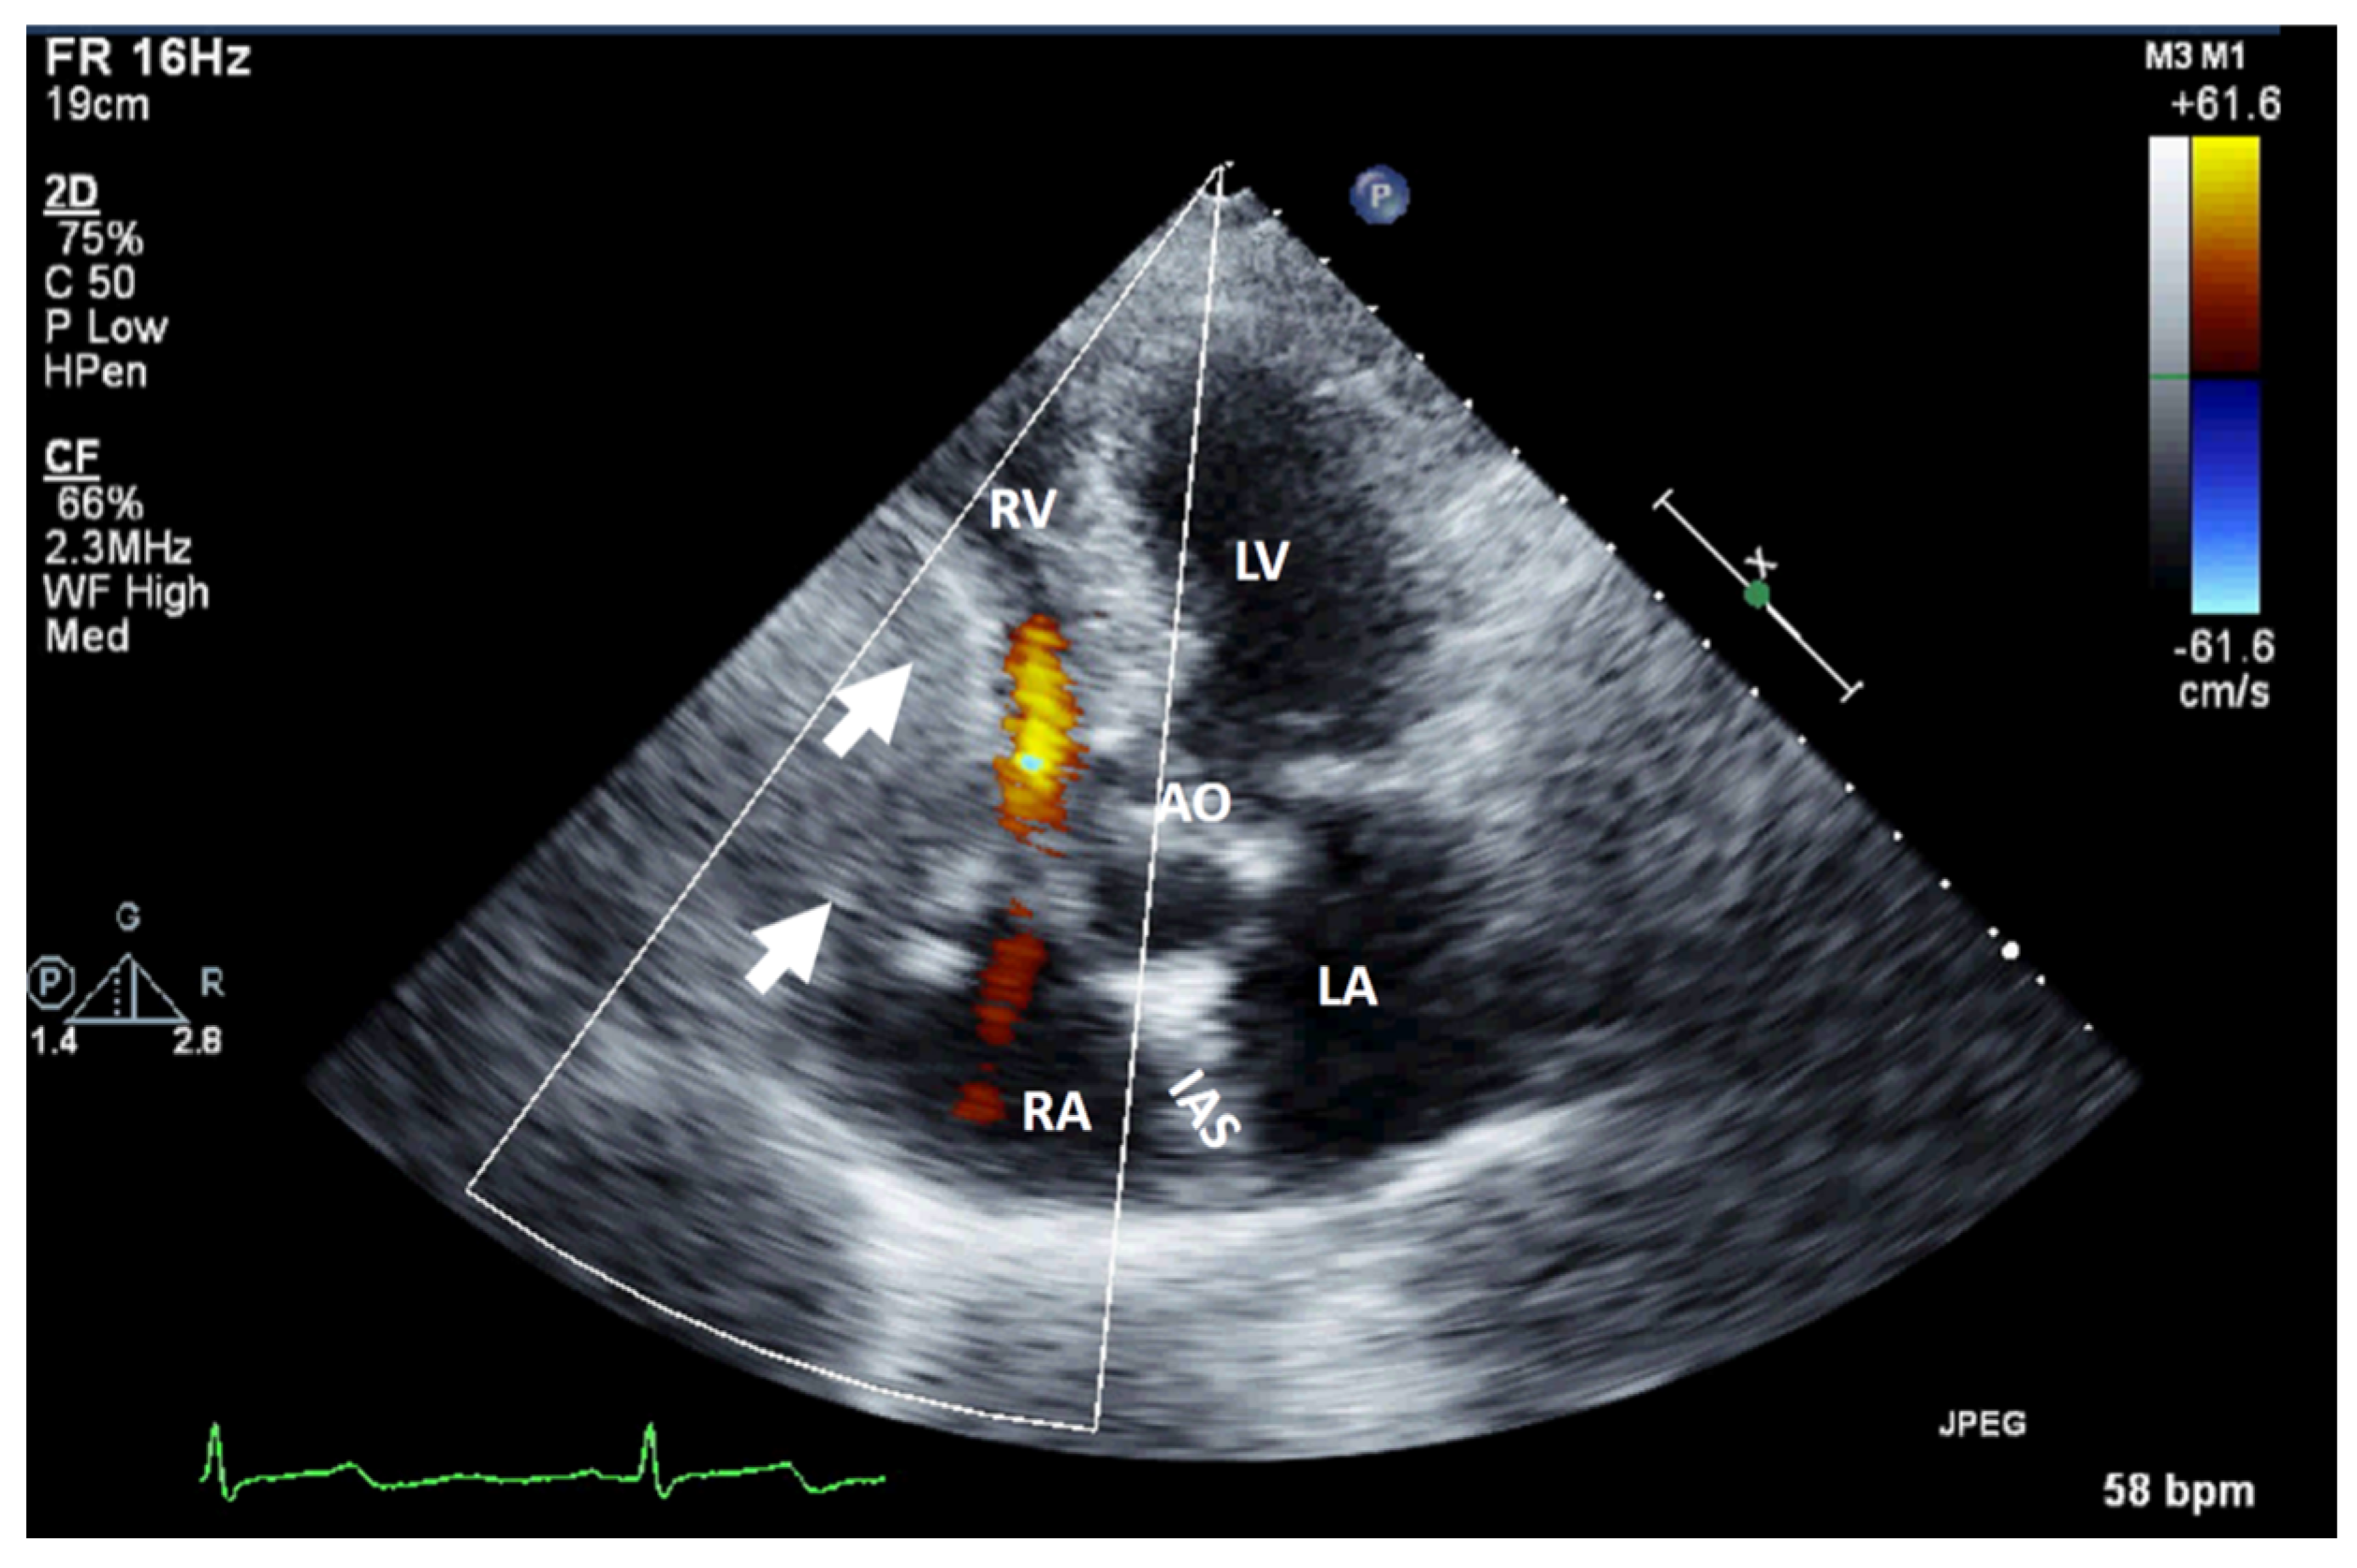

| HEMANGIOMA: It is an incidental finding; if symptomatic, the patient can present with chest pain, arrhythmias, heart failure, dyspnea on exertion, syncope, stroke, pericardial effusion, cardiac tamponade, and even sudden death. | It appears as a well-defined structure, endocardial or intramural, with oscillations during the cardiac cycle, good vascularization (it presents blood flow signals on color Doppler flow imaging), and obvious enhancement. | It is a well-defined structure with low or equal density, associated with heterogeneous intense enhancement and “vascular blush” on coronary angiography. | It appears on T1WI as heterogeneous isointense or hypointense, and on T2WI as hyperintense with heterogeneous enhancement. | It is usually not necessary, except in cases of suspected malignancy. |